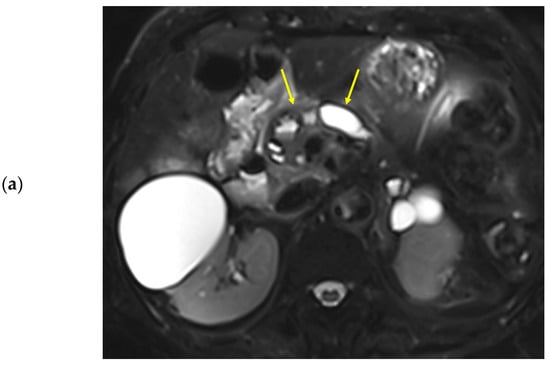

Figure 2.

Seventy-one-year-old female patient undergoing an MRI to evaluate the gall bladder. There is no pancreatic dilatation (arrows) on the T2-weighted imaging (a) and no pancreatic focal lesion. Dynamic contrast-enhanced curves show rapid peak-enhancement and a gradual decrease in enhancement in the head, body, and tail (b).